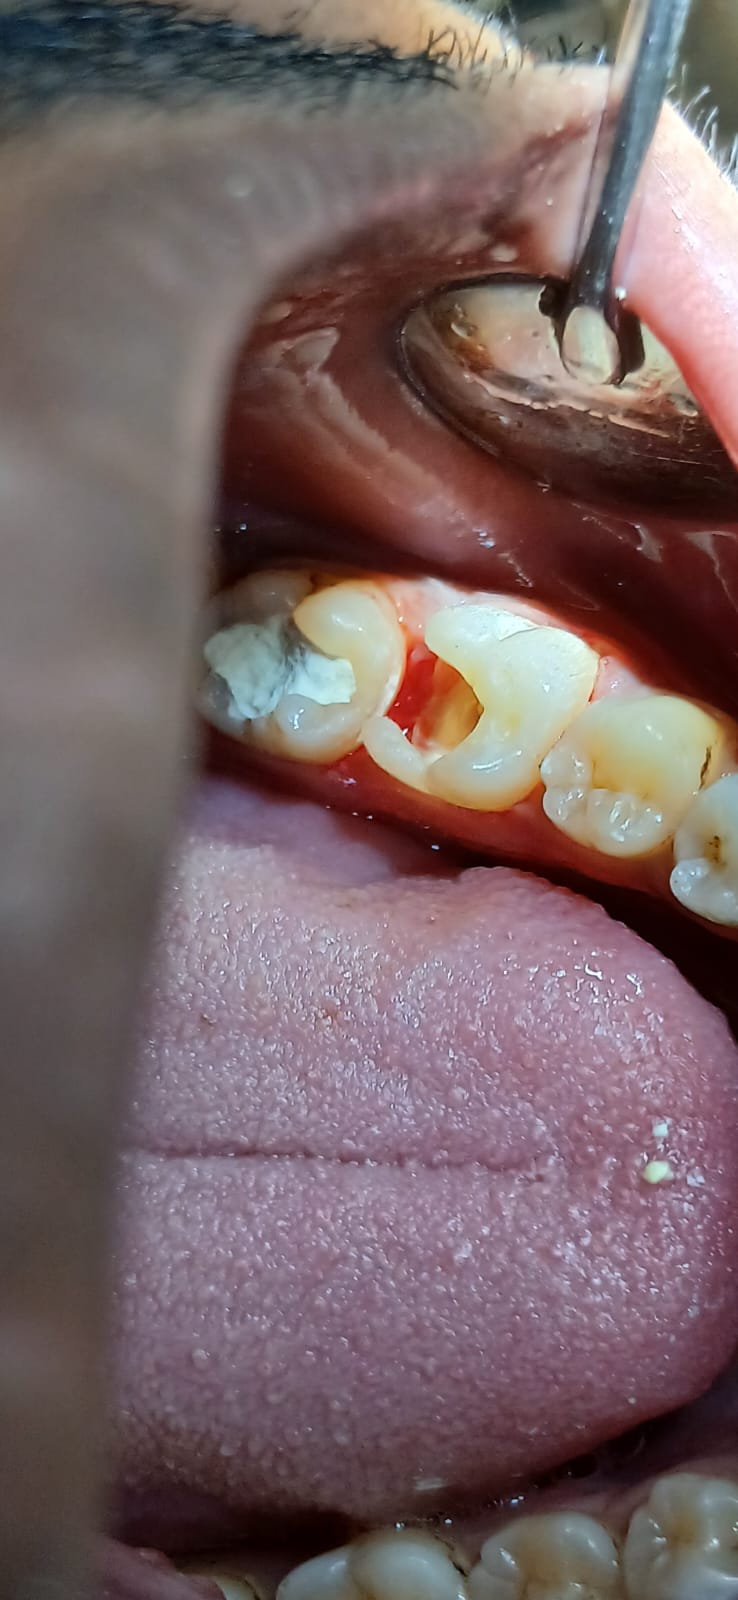

আগে ও পরে

আমাদের সফল কম্পোজিট রেস্টোরেশনের কিছু উদাহরণ

সামনের দাঁতের ক্ষয় মেরামত

ভাঙা দাঁত পুনর্গঠন

দাঁতের ফাঁক বন্ধ

ছবিতে ক্লিক করে বড় করে দেখুন। আরও কেস স্টাডি দেখতে ক্লিনিকে আসুন।